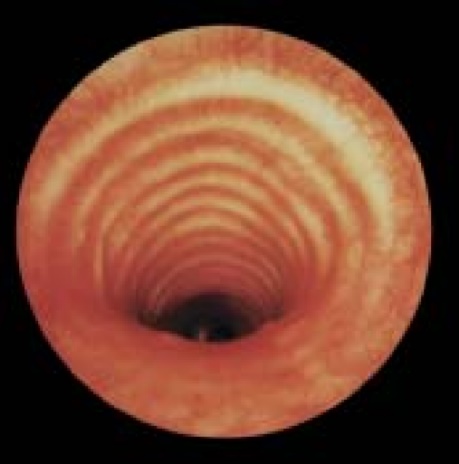

Коллапс трахеи форум